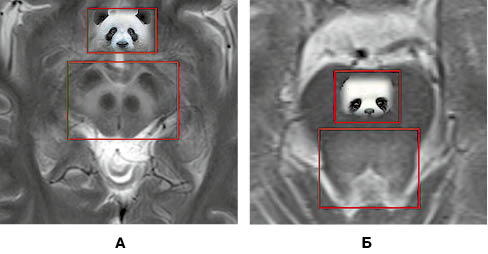

У режимі Т2 візуалізується підвищення МР-сигналу від покришки середнього мозку, на тлі якого спостерігаються чіткі контури червоних ядер і чорної субстанції, створюючи характерний вигляд «голови панди» (ознака «великої панди», рис. 2А). У тому ж режимі на межі середнього мозку та моста, на рівні верхніх мозочкових ніжок візуалізується підвищення сигналу від дорзальних відділів середнього мозку, що створює характерний вигляд «голови малої панди» (ознака «малої панди», рис. 2Б).

При виконання МРТ-дослідження головного мозку пацієнта виявлено типові ознаки хвороби Вільсона у вигляді підвищення МР-сигналу від головок хвостатих ядер, лушпин, блідих куль та таламусів в режимах Т2/Flair і Т2. Також наявне підвищення сигналу від покришки середнього мозку й дорзальних відділів моста (рис. 3).